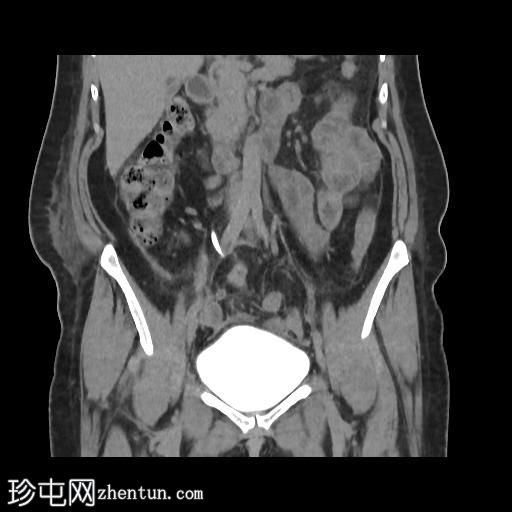

轴位增强扫描(门静脉期)

冠状位肾盂排泄期

CT扫描显示:

左侧膀胱后外侧壁完全撕裂,造影剂外渗至盆腔

盆腔内可见少量积液

腹膜脂肪条索状改变,腹膜反折增厚强化,提示盆腔腹膜炎

腹腔镜

子宫切除术后医源性膀胱损伤伴盆腔腹膜炎的CT表现。